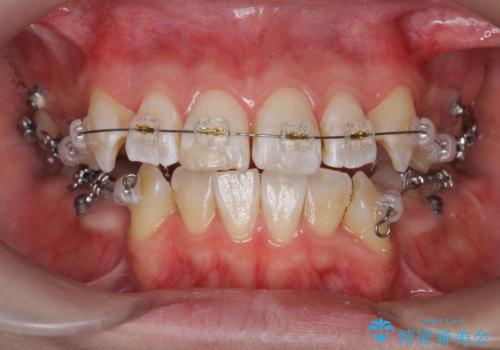

- 矯正装置

- ワイヤー矯正

- 2年8ヶ月

- 突き出て、気になる前歯の角度の改善を求めて来院されました。

前歯の角度を改善するために小臼歯4本の抜歯を行いワイヤー マルチブラケットを用いて、しっかりと前歯の角度を改善する治療計画としました。